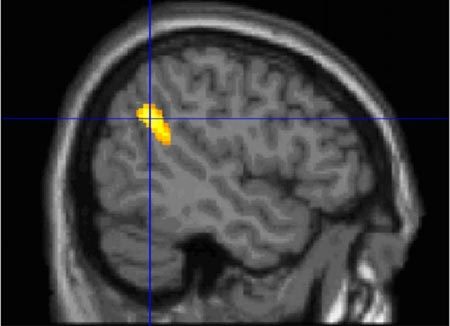

| Nơi tiếp giáp giữa thuỳ đỉnh và thuỳ thái dương (TPJ), một trung tâm xử lý thông tin ở bộ não, liên quan đến sự định hướng chú ý trước các kích thích từ bên ngoài, là nơi con người ghi nhớ các giấc mơ. Ảnh: Daily Mail |

Nhóm nghiên cứu khám phá thấy rằng, vùng giữa vỏ não trước trán (mPFC) và nơi tiếp giáp giữa thuỳ đỉnh và thuỳ thái dương (TPJ), một trung tâm xử lý thông tin ở bộ não, liên quan đến sự định hướng chú ý trước các kích thích từ bên ngoài, hoạt động tích cực hơn ở những người có khả năng nhớ lại giấc mơ cao. Việc tăng hoạt động ở vùng não này được cho là có khả năng tạo điều kiện thuận lợi cho quá trình mã hóa các giấc mơ vào ký ức trong khi chúng ta ngủ.

Trong các nghiên cứu trước đây, nhà tâm lý học thần kinh Nam Phi Mark Solms từng quan sát được rằng, các thương tổn ở 2 vùng não mPFC và TPJ đã dẫn tới việc chấm dứt sự gợi nhớ các giấc mơ.